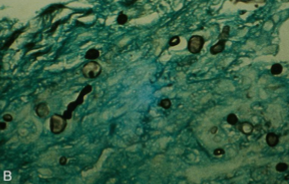

Which sp is this? What is it encapsulated by? What temperature is it at?

Histoplasma capslatum; Monocyte; 37C

Which sp is this? What type of specimen is this? What temperature is it at?

HIstoplasma capsulatum; Tissue; 22C

What is a key feature of Histoplasma capsulatum in mold form?

It can be spikey!